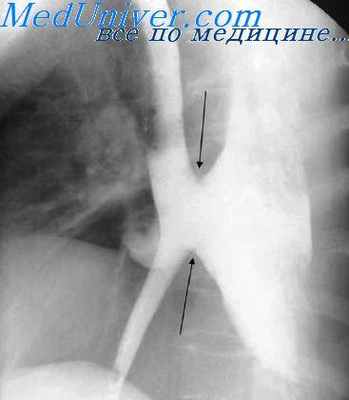

Диффузное сокращение пищевода чаще наблюдается у лиц старше 50 лет. Появление его связывают с дегенеративными изменениями блуждающего нерва. Тонус пищевода при этом значительно повышен, просвет его сужен. Периодически возникающие циркулярные спастические сокращения пищевода чередуются с его расширениями, напоминающими множественные дивертикулы или четки. Иногда спазм захватывает всю среднюю треть пищевода, принимающего при этом вид суженной ригидной трубки, сменяясь затем общим расслаблением мышц пищевода.

Регионарный спазм циркулярных мышц может наступить на любом уровне пищевода. Однако подобные спазмы чаще наблюдаются в естественных местах сужения: в области перехода глотки в пищевод, на уровне дуги аорты, на уровне бифуркации трахеи и в абдоминальном отделе пищевода. Для таких спазмов характерны острое (среди полного благополучия) начало дисфагии, протекающей в виде приступов, непостоянство жалоб больного, смена уровня сужения, а также коническая, симметричная форма сужения.

Спазмы пищевода любой этиологии в рентгенологическом изображении имеют ряд характерных особенностей. Это прежде всего симметричность формы сужения, четкость его контуров, сохранение неизмененного рельефа слизистой оболочки, а также непостоянство сужения, устанавливаемое нередко уже в процессе данного рентгенологического исследования. Спазм абдоминального сегмента пищевода иногда удается снять глотком холодной или горячей воды, изменением положения больного или каким-либо другим приемом.

Рентгеноскопическое исследование. При этом можно обнаружить деформацию пищевода в виде «чёток», «штопора», псевдодивертикулов, а также оценить перистальтику пищевода.